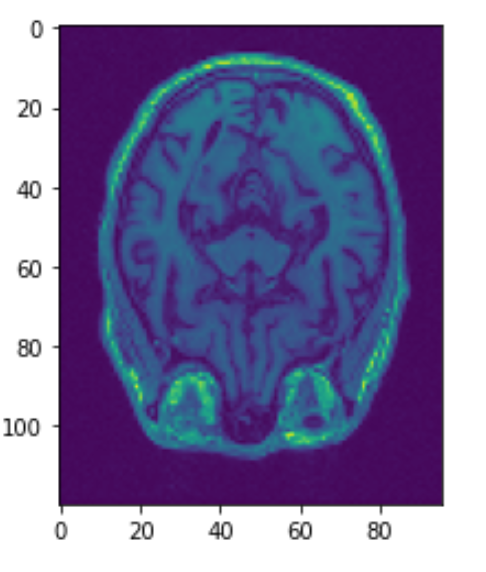

Before any analysis can be done with MRI scans, image registration must be done. Patients can be in many positions when they get their scans. The heads may be slightly tilted or rotated. Image registration normalizes the dataset so that the skulls are somewhat aligned. Below we can see the third image aligned using SimpleElastix. The 2nd image was rotated and moved slightly. The first and third image should line up well.